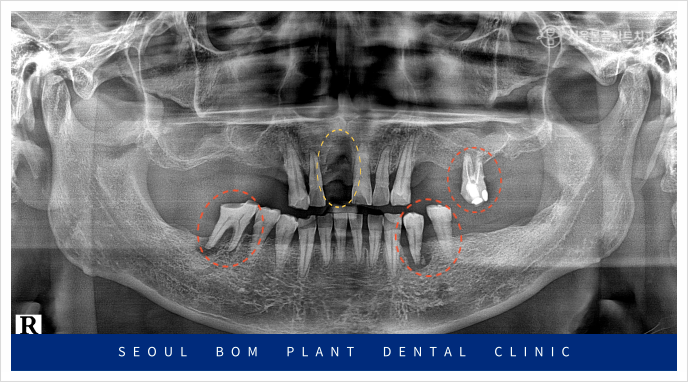

정밀한 검사를 위해

파노라마 사진을 촬영해 보았더니

잇몸뼈 소실로 많이 약해져 있는 상태라

다시 임플란트를 식립하기에는

무리가 있었습니다.

위턱 오른쪽 앞니(#11)의 경우

환자분과 충분한 상담을 통해

양옆의 치아를 이용한

브릿지 보철물을

진행하기로 계획하였는데요.

앞니 외에도 치료가 필요한 부위가

많이 있었는데요.

빨간색 동그라미 표시의

위턱 왼쪽 첫 번째 큰 어금니(#26)와

아래턱 왼쪽 작은 어금니(#34,35)

아래턱 오른쪽 첫 번째 큰 어금니(#46)가

뿌리 끝 염증과 함께 동요도도 심한 상태라

발치가 불가피한 상황이었습니다.